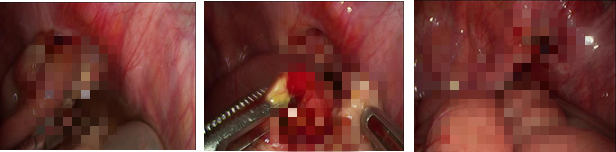

近日,我院甲状腺疝气小儿外科接诊的一名近70岁的女性患者温婆婆,正是闭孔疝的典型病患。温婆婆因腹痛1周在我院就诊,因肠梗阻并腹膜炎症状经多科治疗及检查后,CT结果提示右侧闭孔疝,部分回肠水肿缺血,肠系膜水肿,请我科医师会诊后,转入我科手术治疗。转入我科后,经过短暂而充分的术前准备,立即给温婆婆安排了急诊手术治疗。因考虑温婆婆年纪较大,大外科林唯栋主任、甲状腺疝气小儿外科黄文主任及林贾颖主治医师经讨论后,决定先行微创的腹腔镜探查,术中确诊右侧闭孔疝,部分小肠壁嵌顿并穿孔,遂进行腹腔镜下嵌顿山松解、小肠穿孔修补术,全过程在腹腔镜下进行,难度极大,但手术过程顺利,术时较短,现已康复出院。